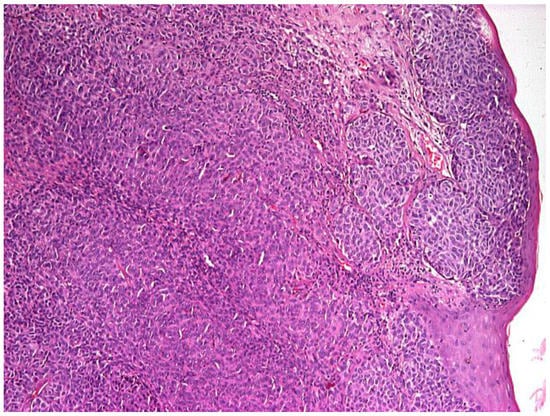

2. Case Report